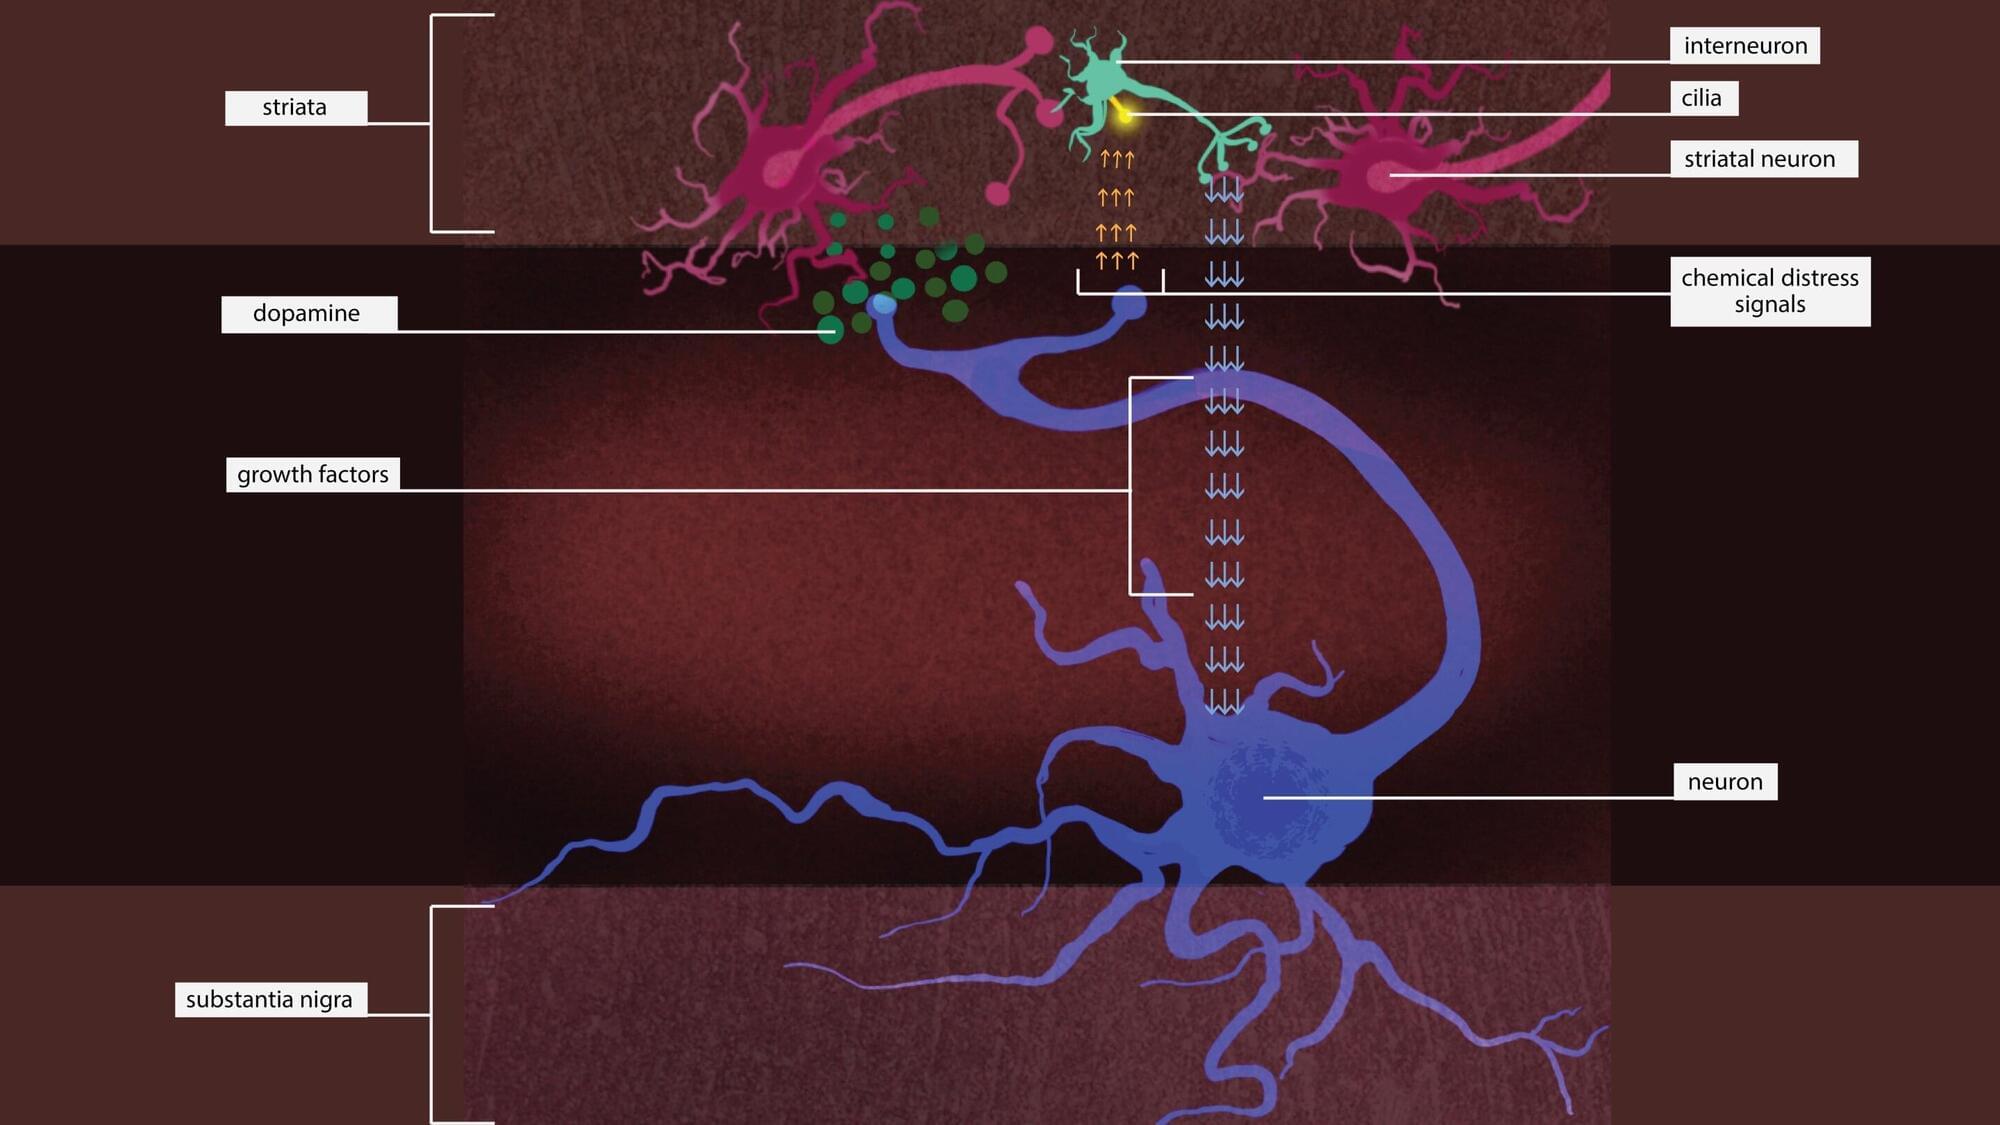

The genetic mutation causes an enzyme called leucine-rich repeat kinase 2, or LRRK2, to be overactive. Too much LRRK2 enzyme activity changes the structure of brain cells in a way that disrupts crucial communication between neurons that make the neurotransmitter dopamine and cells in the striatum, a region deep in the brain that is part of the dopamine system and is involved in movement, motivation and decision-making.